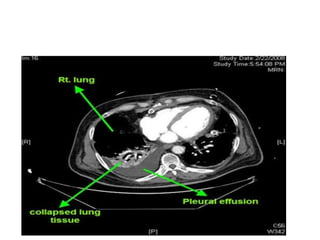

Role of CT scan

• Visualization of underlying lung parenchymal

processes that are obscured on chest

radiographs by large pleural effusions

• Distinguishing empyema from lung abscess

• Help in distinguishing benign from malignant

pleural effusion-pleural nodularity,

mediastinal pleura involvement, pleural

thickening greater than 1 cm.